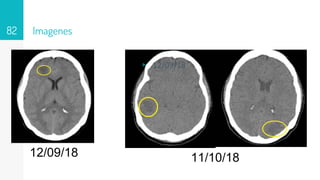

Imagenes

82

12/09/18

▹ 12/09/18

11/10/18

• #83 12 09 18 Area hipodensa en sustancia blaca subcotical en región frontal 20x17 mm 23-32 ud Onfl con dedema perilesional 11 10 18 imagen hipodensa digitiforme en rango 42- 47 Unid Onfil cortico-subcortical en lóbulo frontal derecho, 17.25 und Onfil lóbulo parietan e imagen en región occipital sin aumento de la amplitud de los ventrículos RM 30 10 18 se observan imágenes algunas hipodensas en secuencias T1, otras de señal intermedia muy heterogéneas, hipointensas en secuencias Flair y T2 con realce importante algunas en forma nodular, otras en forma periférica posterior a la administración de gadolinio, las de la región temporal derecha y occipital ipsilateral, con edema perilesional, mucho más importante en la de la región occipital, que debe correlacionarse con antecedente clínico reciente. En el Centro semioval en el lado izquierdo se observan pequeñas imágenes puntiformes hiperintensas en secuencias Flair y T2 pueden corresponder a lesiones vasculares isquémicas de pequeños vasos